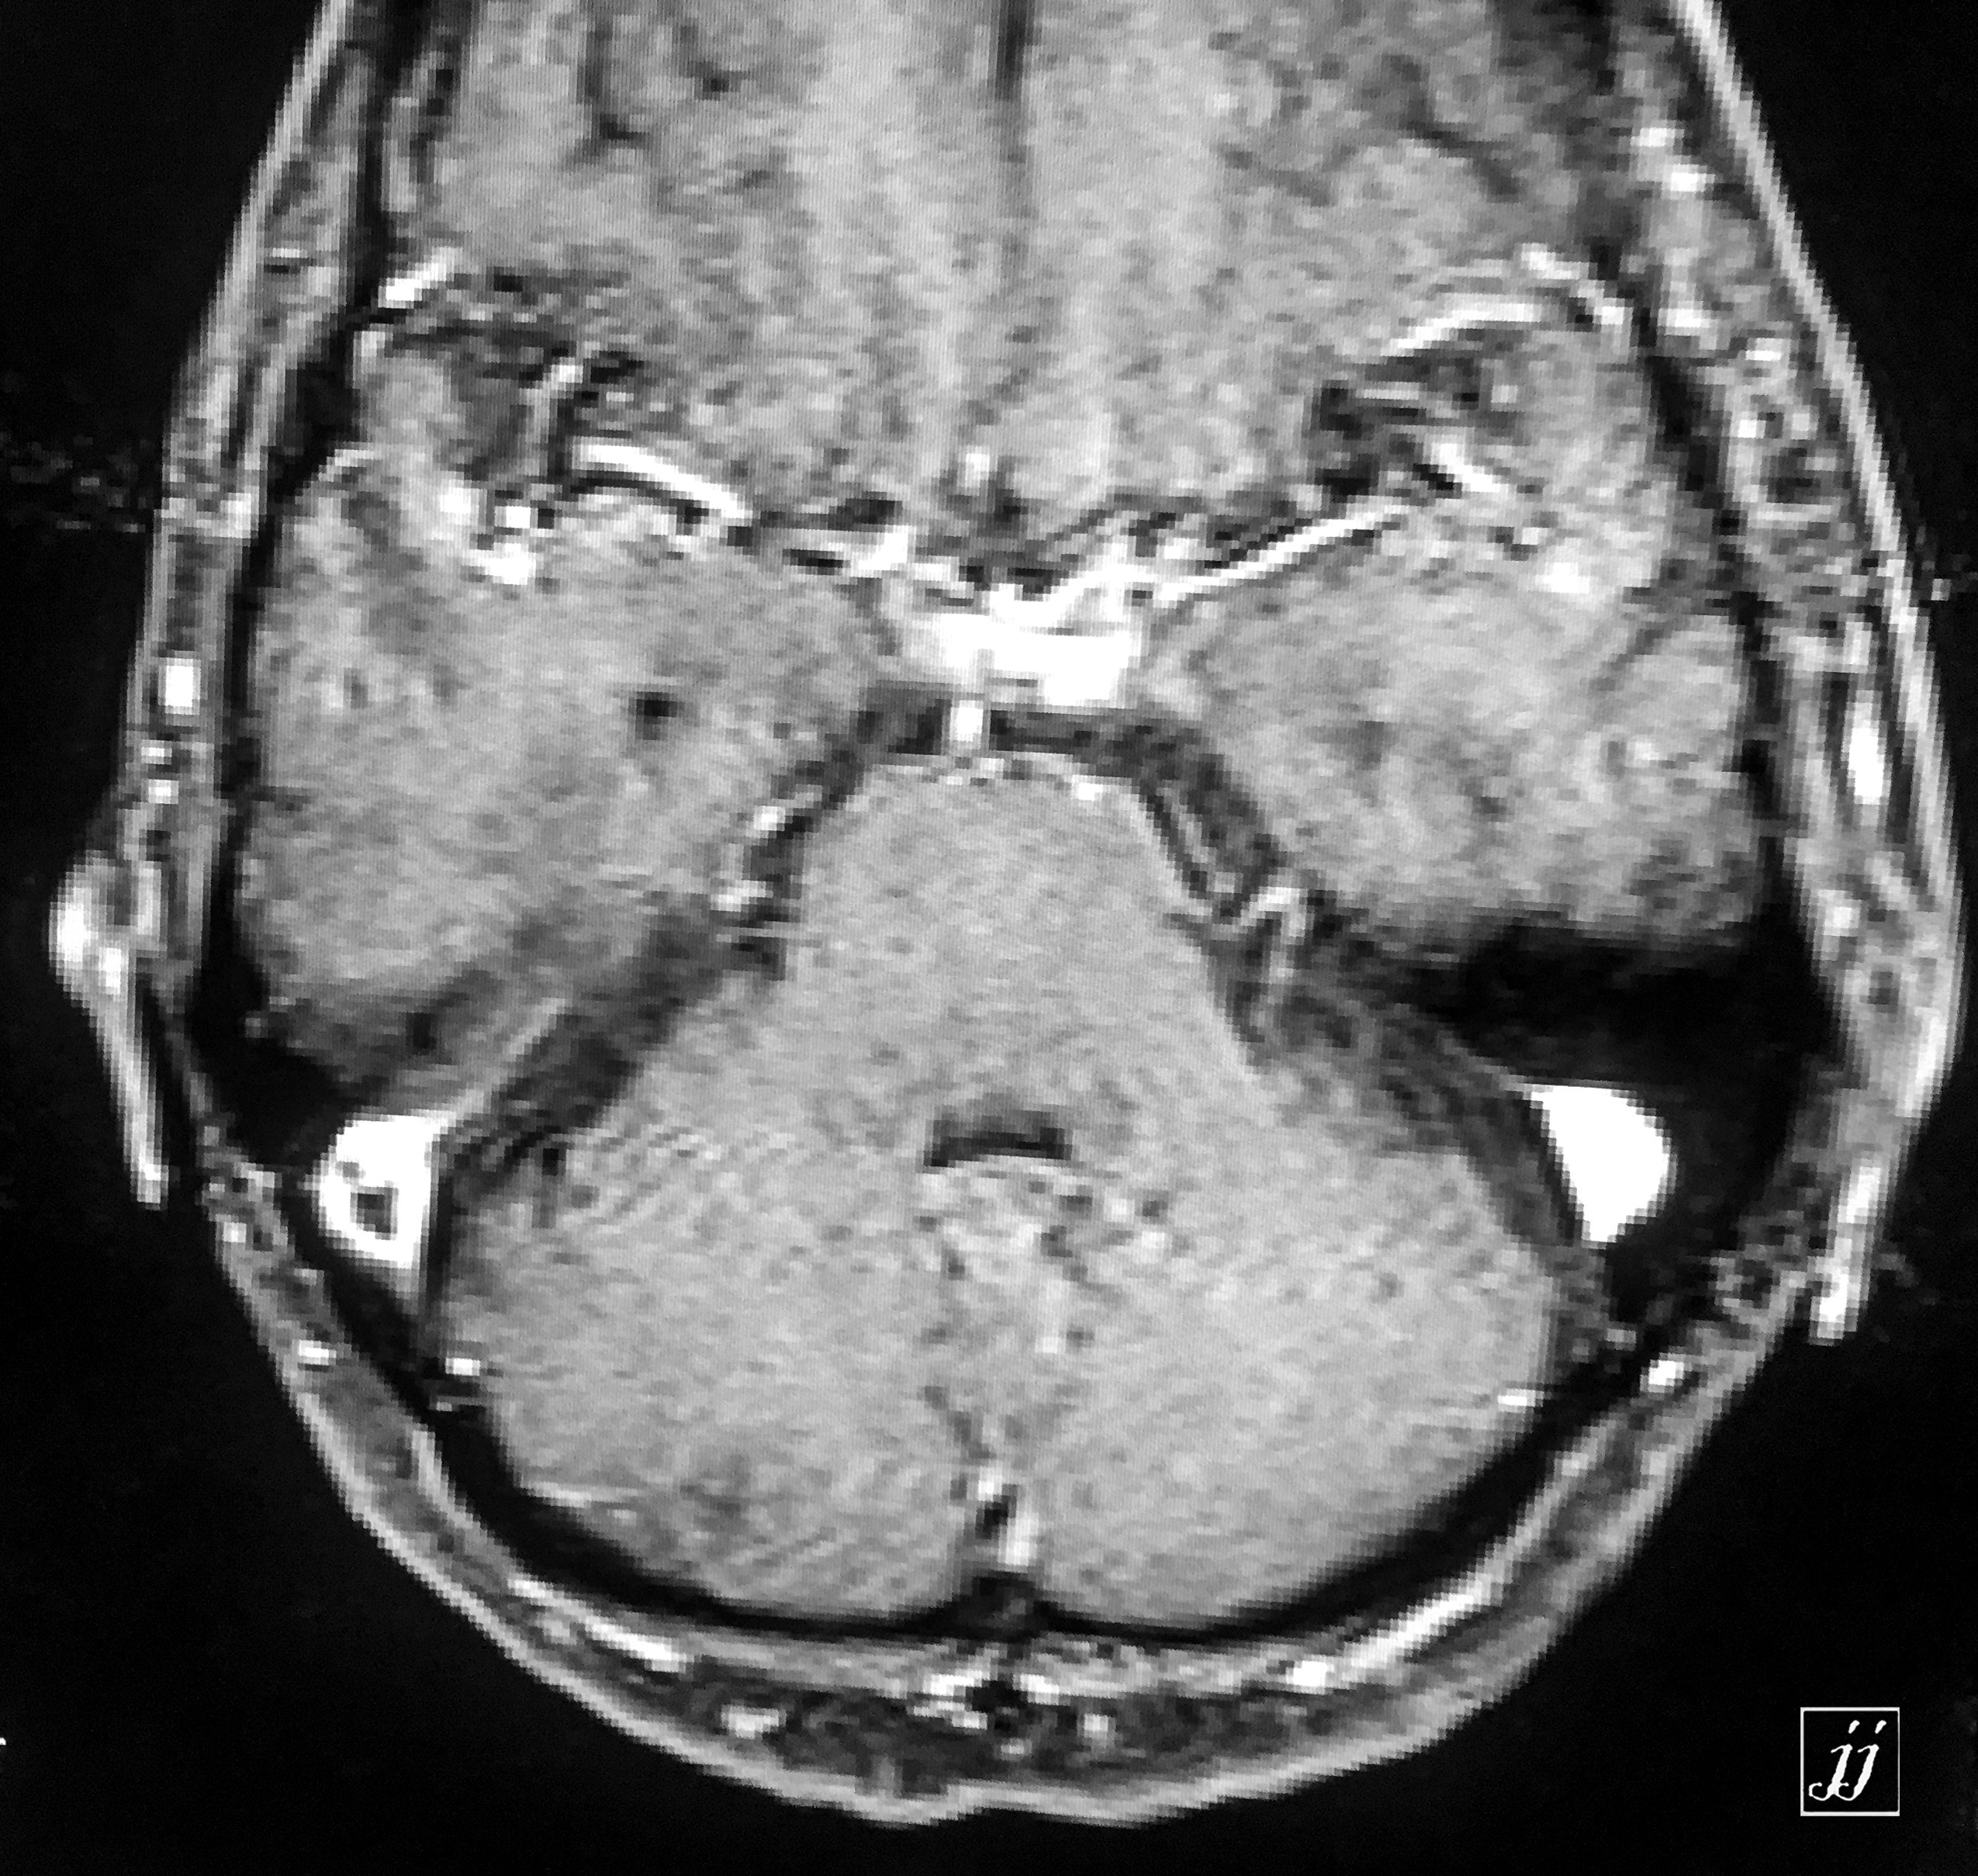

Brain- left mastoid abscess (1)